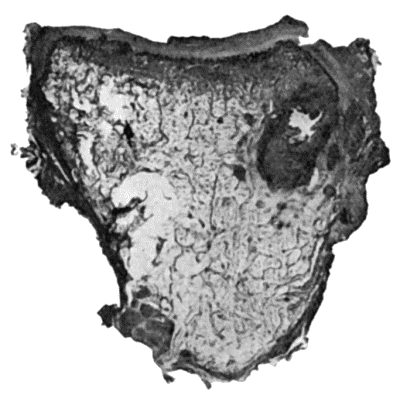

| 114. | Section through Gouty Bursa | 428 |